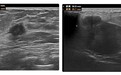

结果提示:左侧乳腺11点及1点方向实性结节,BI-RADS 4C类,右侧乳腺9点方向实性结节,BI-RADS 4a类

乳腺结节4类表示可能存在恶性病变,医生很快给芳姐做了穿刺活检,结果提示:非特殊类型浸润性乳腺癌。